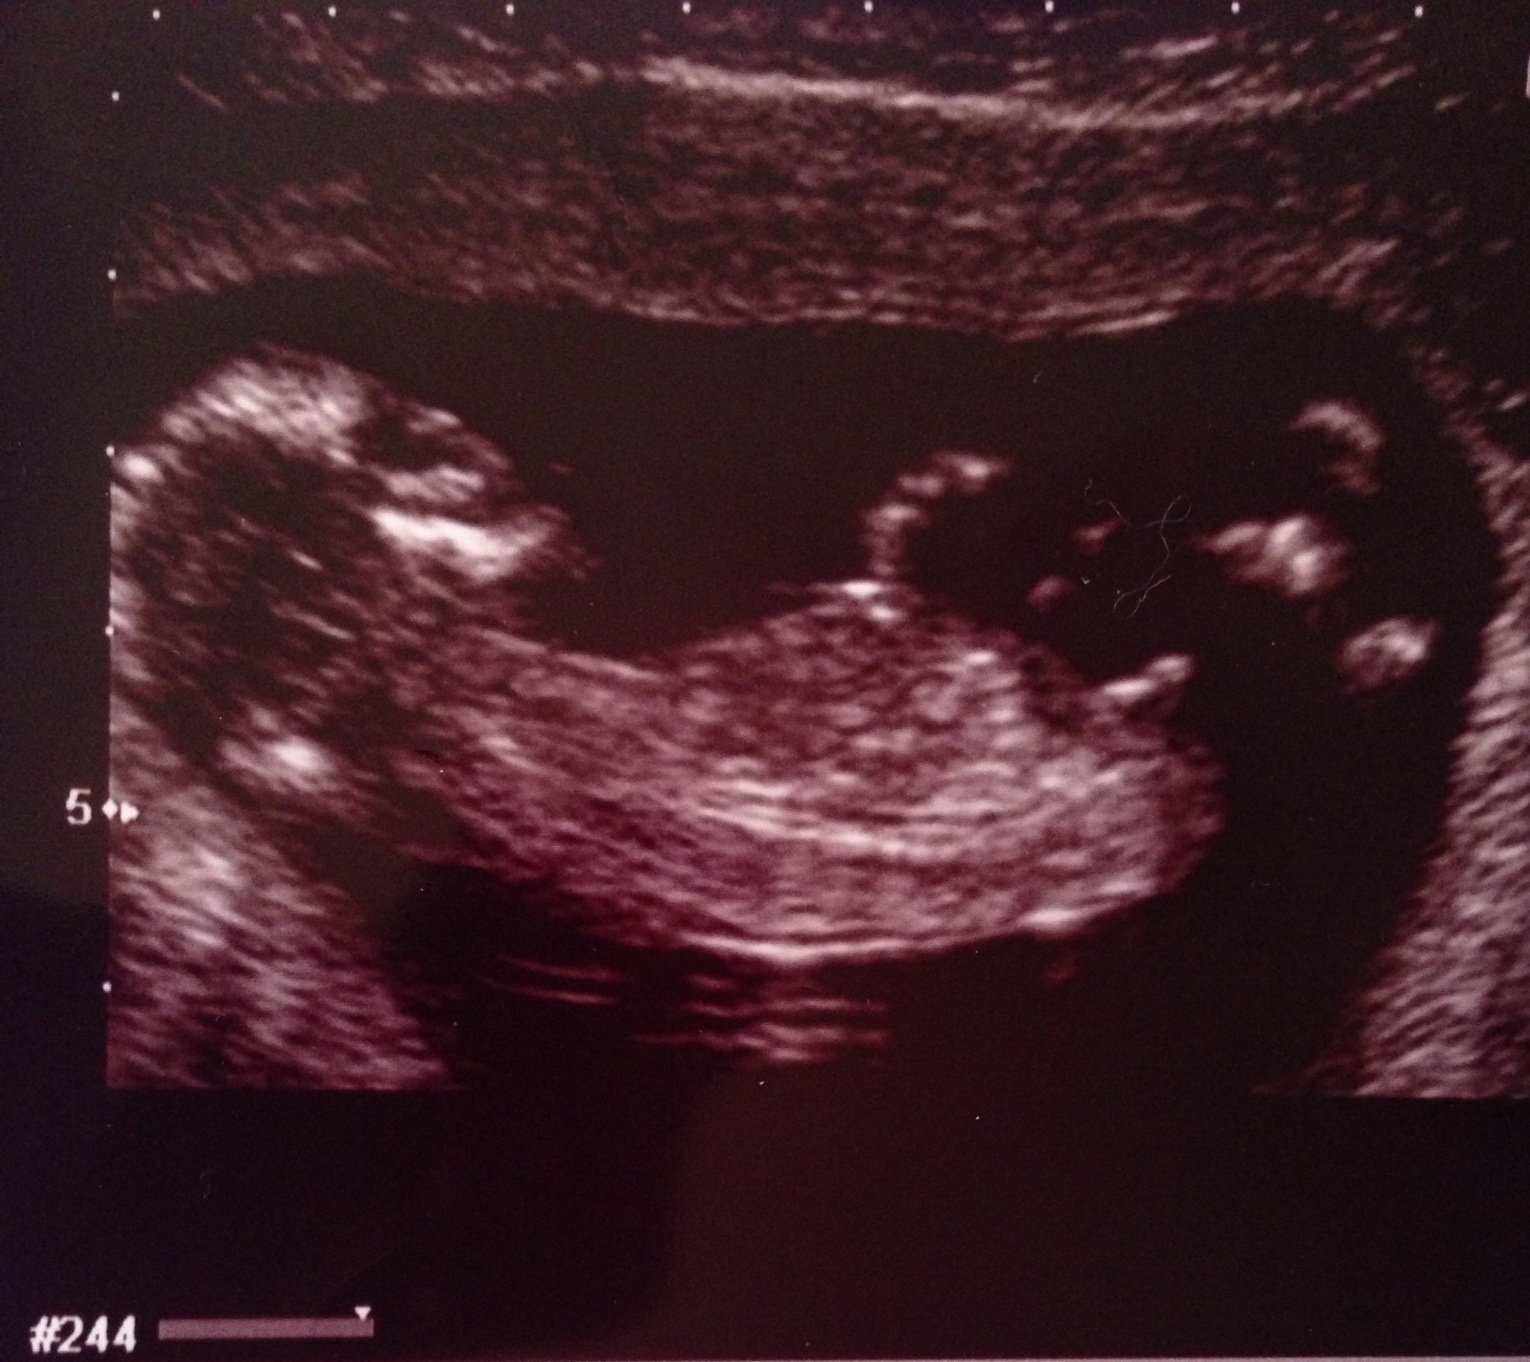

I just had a 12 week ultrasound and am very curious as to the sex of my baby. I will be happy either way. I would just like a healthy baby. Thank you for your help!

Please, help me guess the gender of my first baby! 12 week ultrasound pictures :]

Last picture looks very boyish. Congrats!

The last pic looks very boyish

boy

Definately a boy x

Boy! congrats!